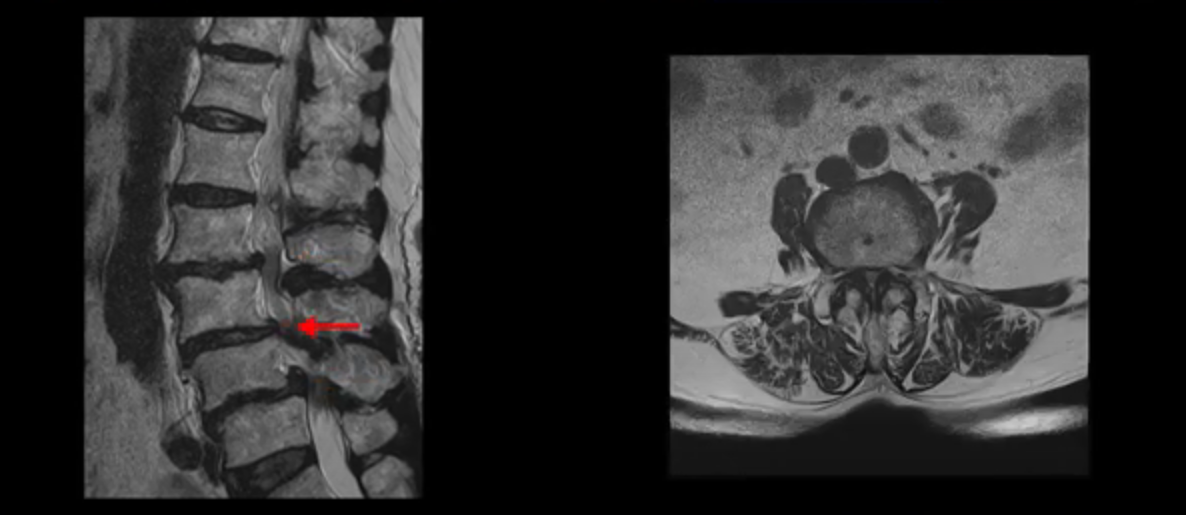

이 환자분 MRI를 보면서 더 자세히 설명 드리겠습니다. 이분은 허리의 다섯 마디가 다 안 좋은 환자분입니다. 84세 고령의 나이에 이렇게 여러 마디가 안 좋으면 대학병원에서도 수술이 어렵다는 얘기를 듣는 경우가 많습니다. 또 수술을 하더라도 결과가 안 좋을 수 있다는 얘기를 들을 가능성이 높습니다.

보시다시피 허리 다섯 마디 전부가 다 퇴행되어 있고,

두 마디에 전방전위증이 있고,

2번 3번,

3번 4번,

4번 5번에 중심성 협착이 심하고

거의 모든 추간공 즉, 신경가지가 좌우로 빠져나가는 구멍이 다 좁아져 있습니다.

척추가 이런 상태니까 양쪽 엉치와 다리가 다 저리고 아프며 지팡이를 짚고 겨우 걷는 상태였습니다. 이렇게 국내 최상위 대학병원에서도 수술하지 말라고, 수술하면 더 안 좋을 거라는 얘기를 들은 고령의 말기 협착증 환자가 근육 재활치료로 좋아질 수 있을까요? 당연히 좋아질 수 있습니다. 무슨 근거로 이렇게 자신있게 얘기하는 걸까요? 왜냐하면 근육이 좋아지는 만큼 협착증 증상이 좋아지기 때문입니다. 근육은 뭉친 걸 반복해서 풀어주고 환자 상태에 맞는 적절한 운동을 잘 하는만큼 좋아질 가능성이 매우 높습니다. 저희는 수많은 치료 후기와 임상시험을 통한 국제학술 논문 등을 통하여 이렇게 여러 마디가 안 좋은 고령의 말기 협착증 환자분들도 근육을 치료하여 근육 상태가 좋아지면 협착증 증상이 좋아진다는 걸 계속해서 보여드리고 있습니다.